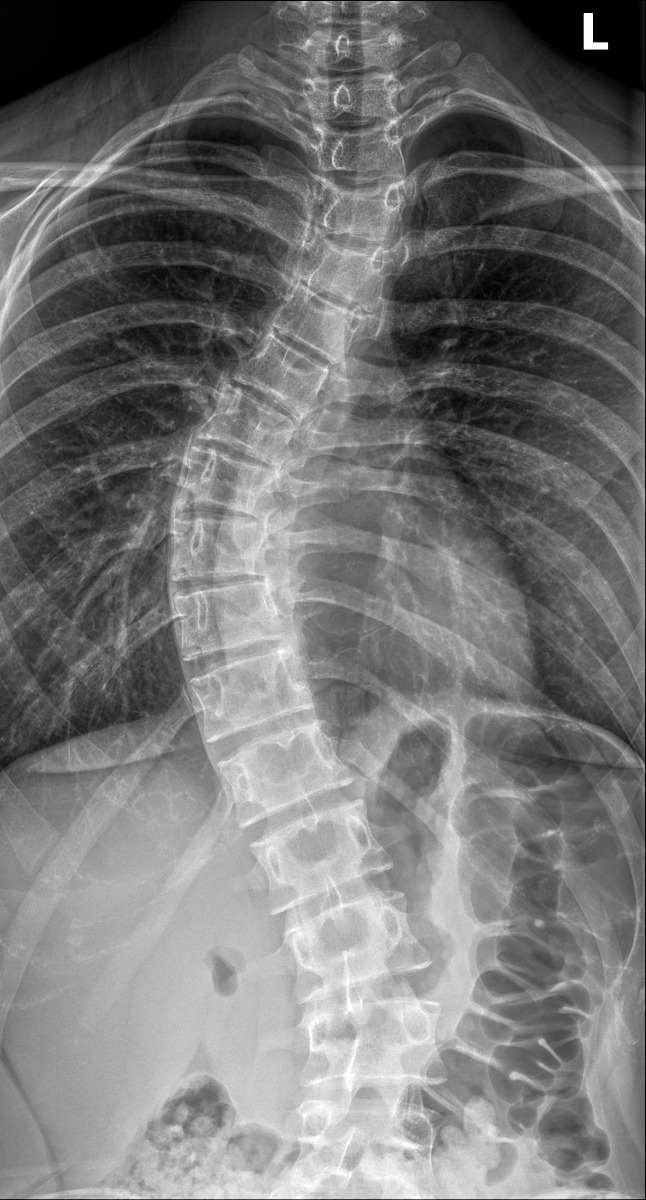

Die Skoliosekorrektur von Jugendlichen ist eine riskante Operation. Nicht nur weil das neurologische Outcome für das ganze zukünftige Leben auf dem Spiel steht, sondern auch weil mit dem meist hohen Transfusionsbedarf ein weiterer bislang nicht einschätzbarer Risikofaktor in Kauf genommen werden muss. In einer retrospektiven Studie hat nun ein griechisches Autorenteam den Einfluss eines 3-Komponenten-Programms bestehend der Steuerung des Volumen- und Transfusionsbedarfs mittels Schlagvolumenanalyse, der Einsatz von Tranexamsäure und maschineller Autotransfusion getestet ...